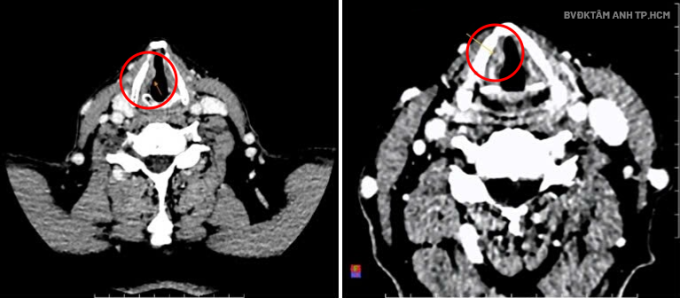

Nội soi tai mũi họng tại Bệnh viện Đa khoa Tâm Anh TP HCM cho thấy hai dây thanh của ông Bình phù nề, dây thanh phải sùi, sụn phễu sung huyết. Kết quả CT ghi nhận tổn thương ở thanh quản, ngang mức ở dây thanh bên phải, dạng sùi, kích thước khoảng 7x14x6 mm. Giải phẫu bệnh xác định ung thư biểu mô tế bào vảy xâm nhập độ hai, giai đoạn T2.

GS.TS.BS Trần Phan Chung Thủy, Giám đốc Trung tâm Tai Mũi Họng, cho biết ông Bình mắc ung thư thanh quản, tổn thương từ lớp tế bào vảy ở vùng thanh quản. Khối u xâm lấn vào mô xung quanh độ hai về mức độ biệt hóa, mức ác tính trung bình, hạn chế vận động dây thanh, xâm lấn vùng cạnh thanh môn nhưng chưa di căn xa.